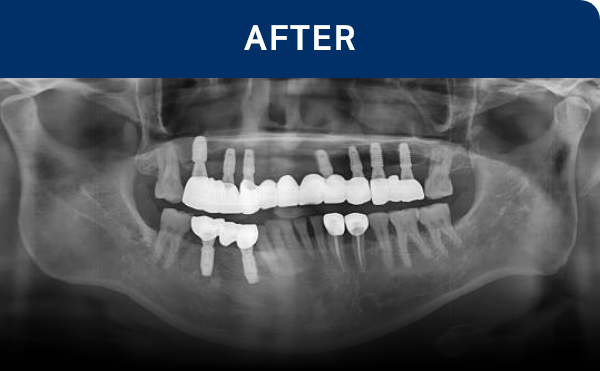

전후가 명확한 결과, 그 결과가

곧 신길플란트치과의 신뢰입니다.

불편함 없이 웃고, 걱정 없이 드실 수 있도록 임플란트로 일상의 편안함을 되찾아드리겠습니다.